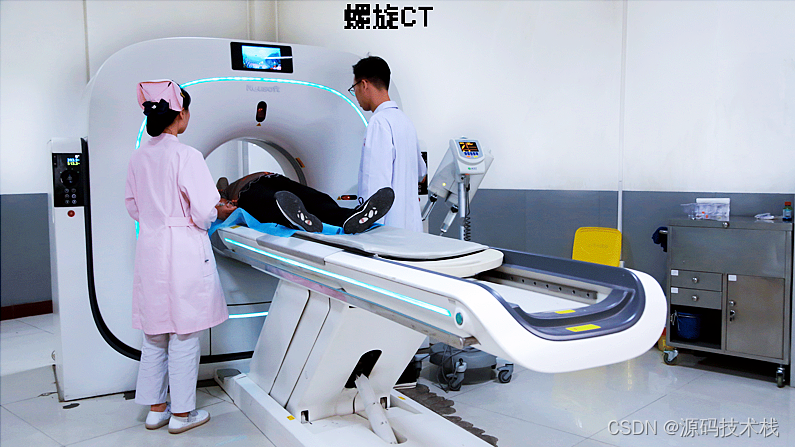

三维重建是多层螺旋CT的一个最大的优点,也是影像工作多年来,从横断解剖到多平面,乃至立体的一次飞跃,让抽象变的形象,大大地提高了准确性,为临床工作的开展,注入了无限生机,从而解决许多临床上,无法开展的一些难题。